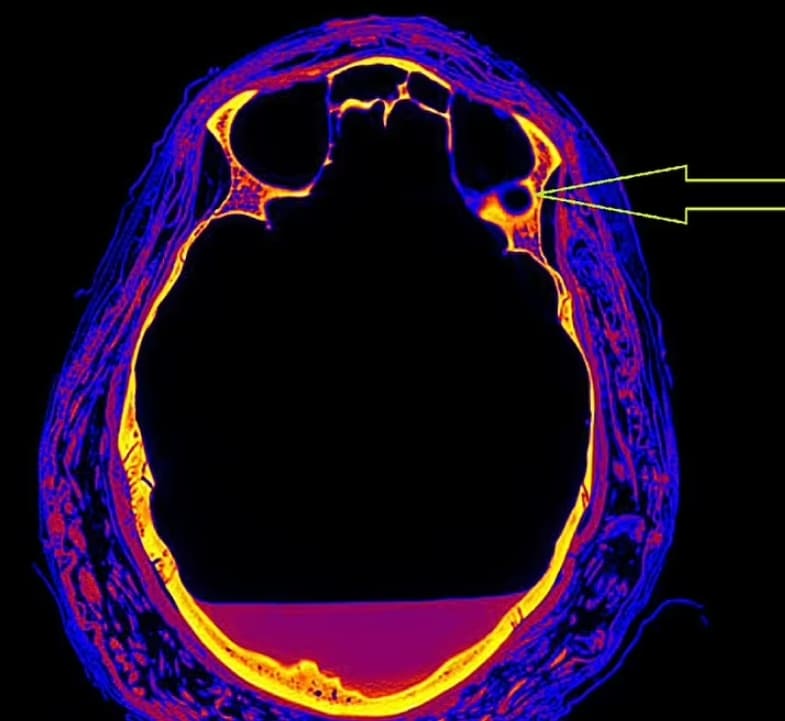

폴란드의 연구원들은 이 고대 시체의 두개골을 스캔하던 중 뼈에서 특이한 자국을 발견했다.

폴란드의 바르샤바 미라 프로젝트 (WMP)에 의해 공개된 이미지들은 종양에 의해 생긴 병변과 미라 시술 동안 보통 형성되지 않는 뼈의 부분에 큰 결함이 있는 두개골을 보여준다.

WMP에서 전문가들과 함께 일했던 바르샤바 의과대학 종양학과의 라파슈 스테크 교수는 "미라 전문가들에 따르면 비인두 뼈에 특이한 변화가 있다"고 말했다.

'두 번째로, 컴퓨터 단층촬영에 기초한 방사선 전문의들의 의견은 뼈의 종양 변화 가능성을 보여준다.'